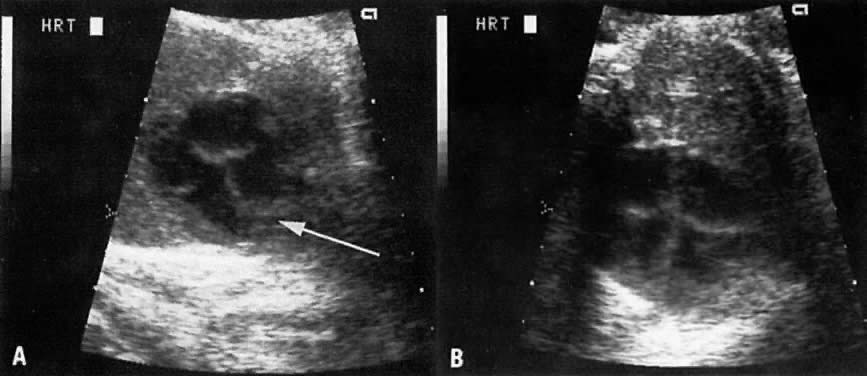

Great Vessel View

The great vessel view depicts the relatively parallel relationship of the superior vena cava, aorta, and pulmonary arteries after the latter two cross each other (Fig. 8). Clear visualization of this plane indicates that the crossing of the aorta and pulmonary artery is normal and virtually rules out transposition of the great vessels. Aortic or pulmonary stenosis also can be recognized in this view.

Fig. 8. A. Schematic drawing of the crossing of the pulmonary artery (PA) and the aorta (Ao) . Note how the branch of the pulmonary artery passes below the aorta (see Fig. 7). The black line is the plane that shows the great vessel view (GVV) depicting the almost parallel relationship between the superior vena cava (SVC), PA, and Ao. B. Echogram of the GVV showing the almost parallel relationship between the SVC, P/A, and Ao. C. Echogram of GVV showing aortic stenosis with very small aortic outflow (A outflow) and a normal-sized pulmonary artery. (DA = ductus arteriosus)

In truncus arteriosus, the pulmonary artery is not clearly depicted by ultrasound. Instead, the aortic outflow tract is large and the aorta is overriding.

The great vessel view also allows a comparative measurement of the two arteries a short distance beyond the valvular level; the measurements should be obtained from the inner aspects of these arteries. Normally the ratio of pulmonary artery: aorta has a mean value of 1.09 (range = 0.75 to 1.43) and is independent of gestational age.24

Intravenous administration of furosemide (40 mg IV) has not been helpful in differentiating renal agenesis from severe intrauterine growth restriction. Further, because of associated oligohydramnios as well as an enlarged adrenal gland that mimics renal appearance, the diagnosis by gray scale ultrasound is difficult (sensitivity, 50%).51 In suspected cases, however, the use of color Doppler velocimetry may show absence of renal arteries in bilateral renal agenesis and only one renal artery in the unilateral form of this abnormality (Fig. 17).52

Fig. 17. A. Cross-section of fetal abdomen at level of kidneys (spine anterior, arrow) shows both kidneys. The areas on each side of the spine are filled with a uniform echopattern, and no kidneys are seen. B. Color Doppler of aorta in a fetus with renal agenesis fails to outline renal arteries.

4. Aneurysm of the vein of Galen (Fig. 25):70 Dilation of the vein of Galen results from an arteriovenous malformation in which one or more arterioles feed the vein of Galen and distend it. The diagnosis is clarified by color Doppler velocimetry (see Fig. 25). The distension may result in hydrocephaly, and it may lead to high-output cardiac failure (see Fig. 25).

Fig. 25. A. Echogram showing malformation of the vein of Galen (arrow). B. Color Doppler velocimetry confirms lesion, showing turbulent flow (cursor) due to arterial blood flow into the vein. C. Great vessel view of fetus with right heart failure secondary to a vein of Galen malformation. Note dilated pulmonary artery (X) below aorta (+). The superior vena cava above the aorta enters into a dilated right ventricle.